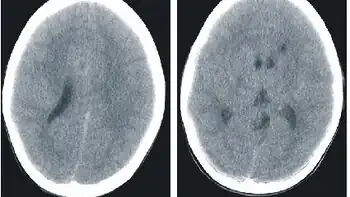

.jpg)

Histidenemia is characterized by increased levels of histidine, histamine and imidazole in blood, urine and cerebrospinal fluid. This also results in decreased levels of the metabolite urocanic acid in blood, urine, and skin cells.[1]